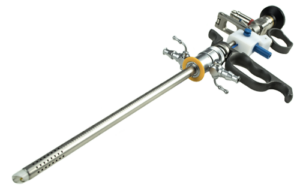

Nefroscopio

Telescopio Panoview con ocular desplazado lateralmente, dirección de visión de 12° y canal de trabajo de 6 Fr.